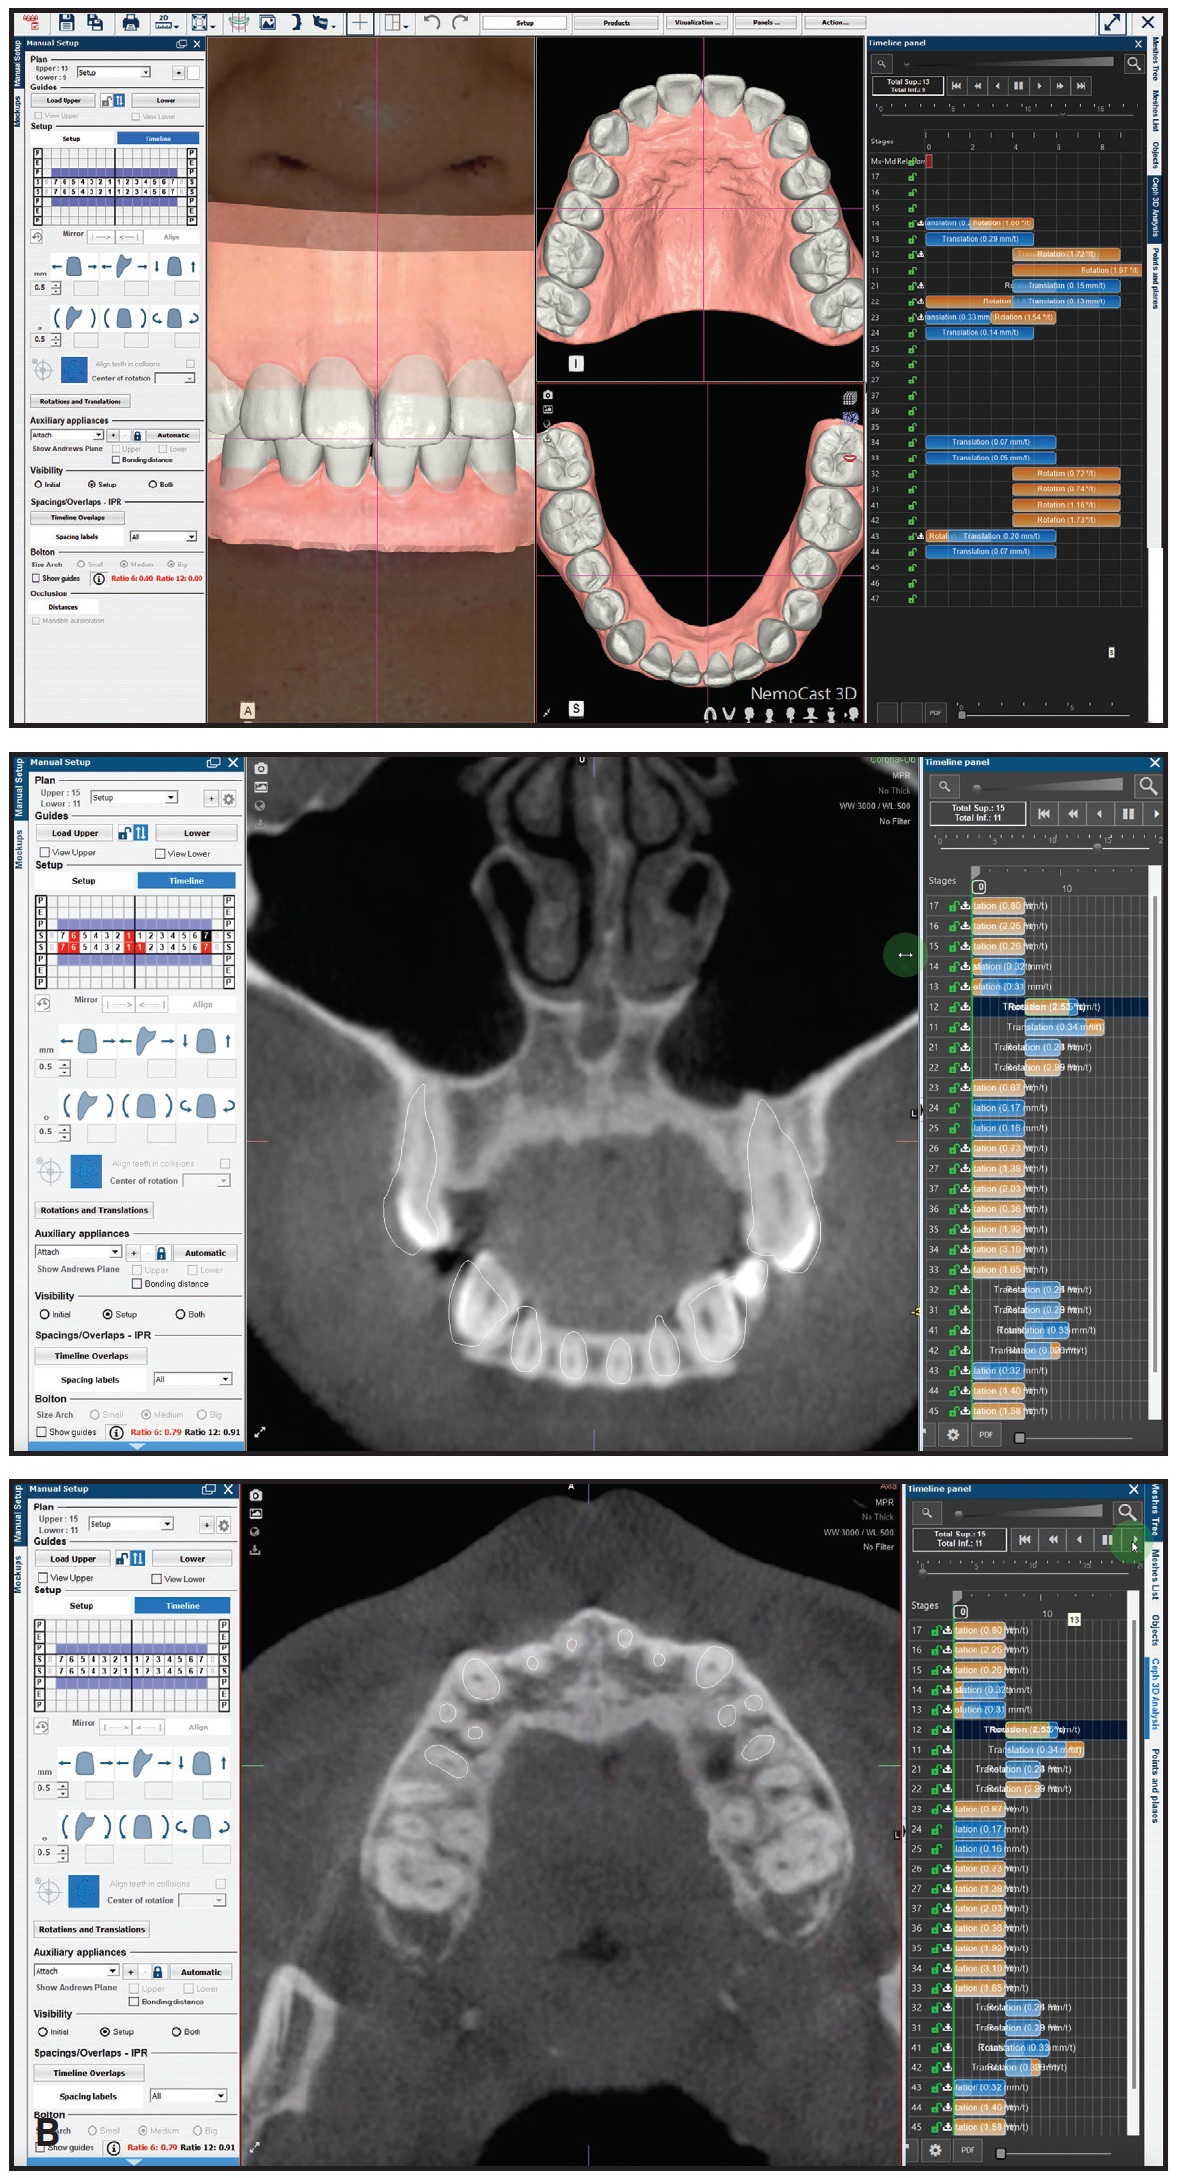

Direct-printed aligners provide orthodontists with enough flexibility to maintain full control over the treatment workflow ([img=5A]Fig. 5A, 5B and 5C).

Fig. 5 Sample case treated with combination of enamel reduction, slight expansion, and uprighting. A. Patient with Class I relationship and anterior crowding before treatment. B. Planning and staging performed in NemoStudio‡ software (continued in next image).

Fig. 5 (cont.) Sample case treated with combination of enamel reduction, slight expansion, and uprighting. B. Planning and staging performed in NemoStudio‡ software (continued in next image).

Fig. 5 (cont.) Sample case treated with combination of enamel reduction, slight expansion, and uprighting. C. Progress of treatment with 17 sets of aligners. D. Final results after four months of treatment.